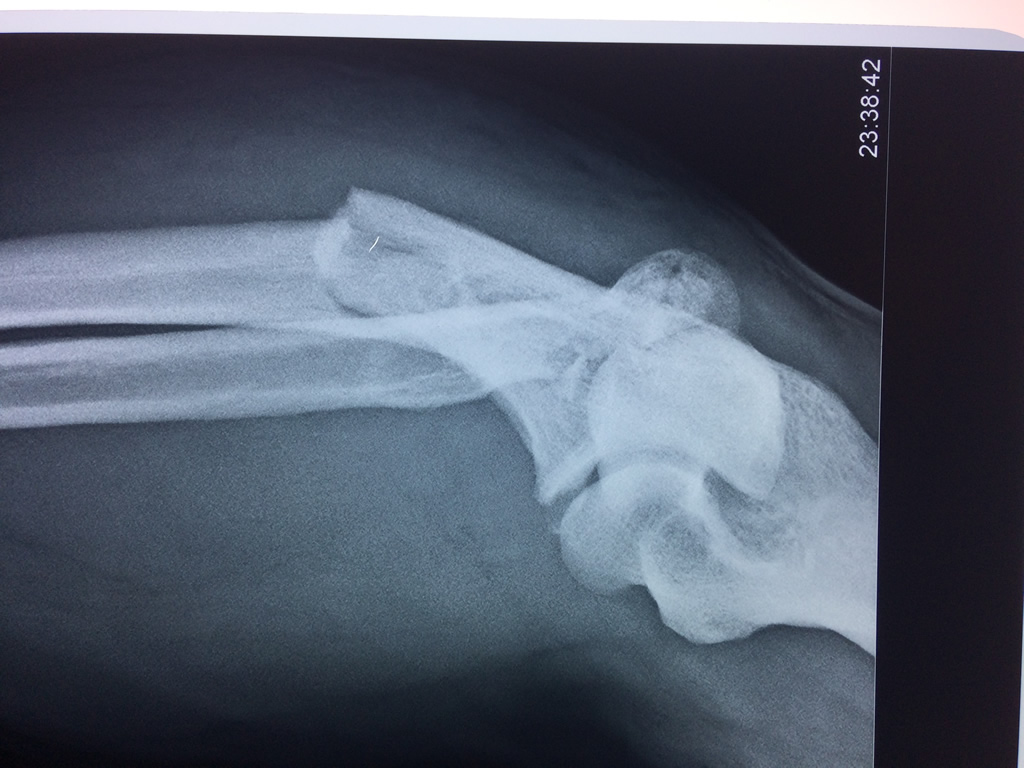

En anatomía humana, la articulación del codo es la que une el brazo con el antebrazo, conectando la parte distal del hueso húmero con los extremos proximales de los huesos cúbito y radio.

La articulación principal que constituye el codo se denomina humero radio-cubital y puede dividirse en dos partes bien diferenciadas, la articulación humero-radial y la humero-cubital.

Por otra parte el cúbito y el radio forman también una articulación entre si en las proximidades del codo, la cual se denomina articulación radio-cubital proximal.

Los extremos óseos se conectan entre si por un conjunto de ligamentos que contribuyen a su fijación y están rodeado por una estructura común que se llama cápsula articular, en cuyo interior se encuentra el líquido sinovial.

En el lenguaje común se le da el nombre de codo a la parte posterior y prominente situada en la unión del brazo con el antebrazo.